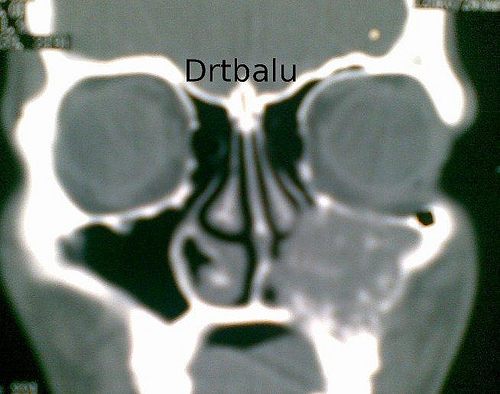

Coronal CT scan nose and sinuses showing fungal sinusitis of maxillary sinus